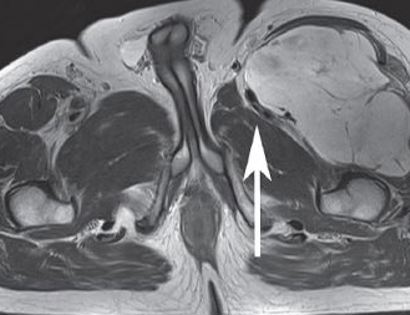

MRI of quadriceps tumor

This MRI shows a large mass on the upper left hand side of the thigh (upper right hand side of the image) which is compressing the muscles and nerves.